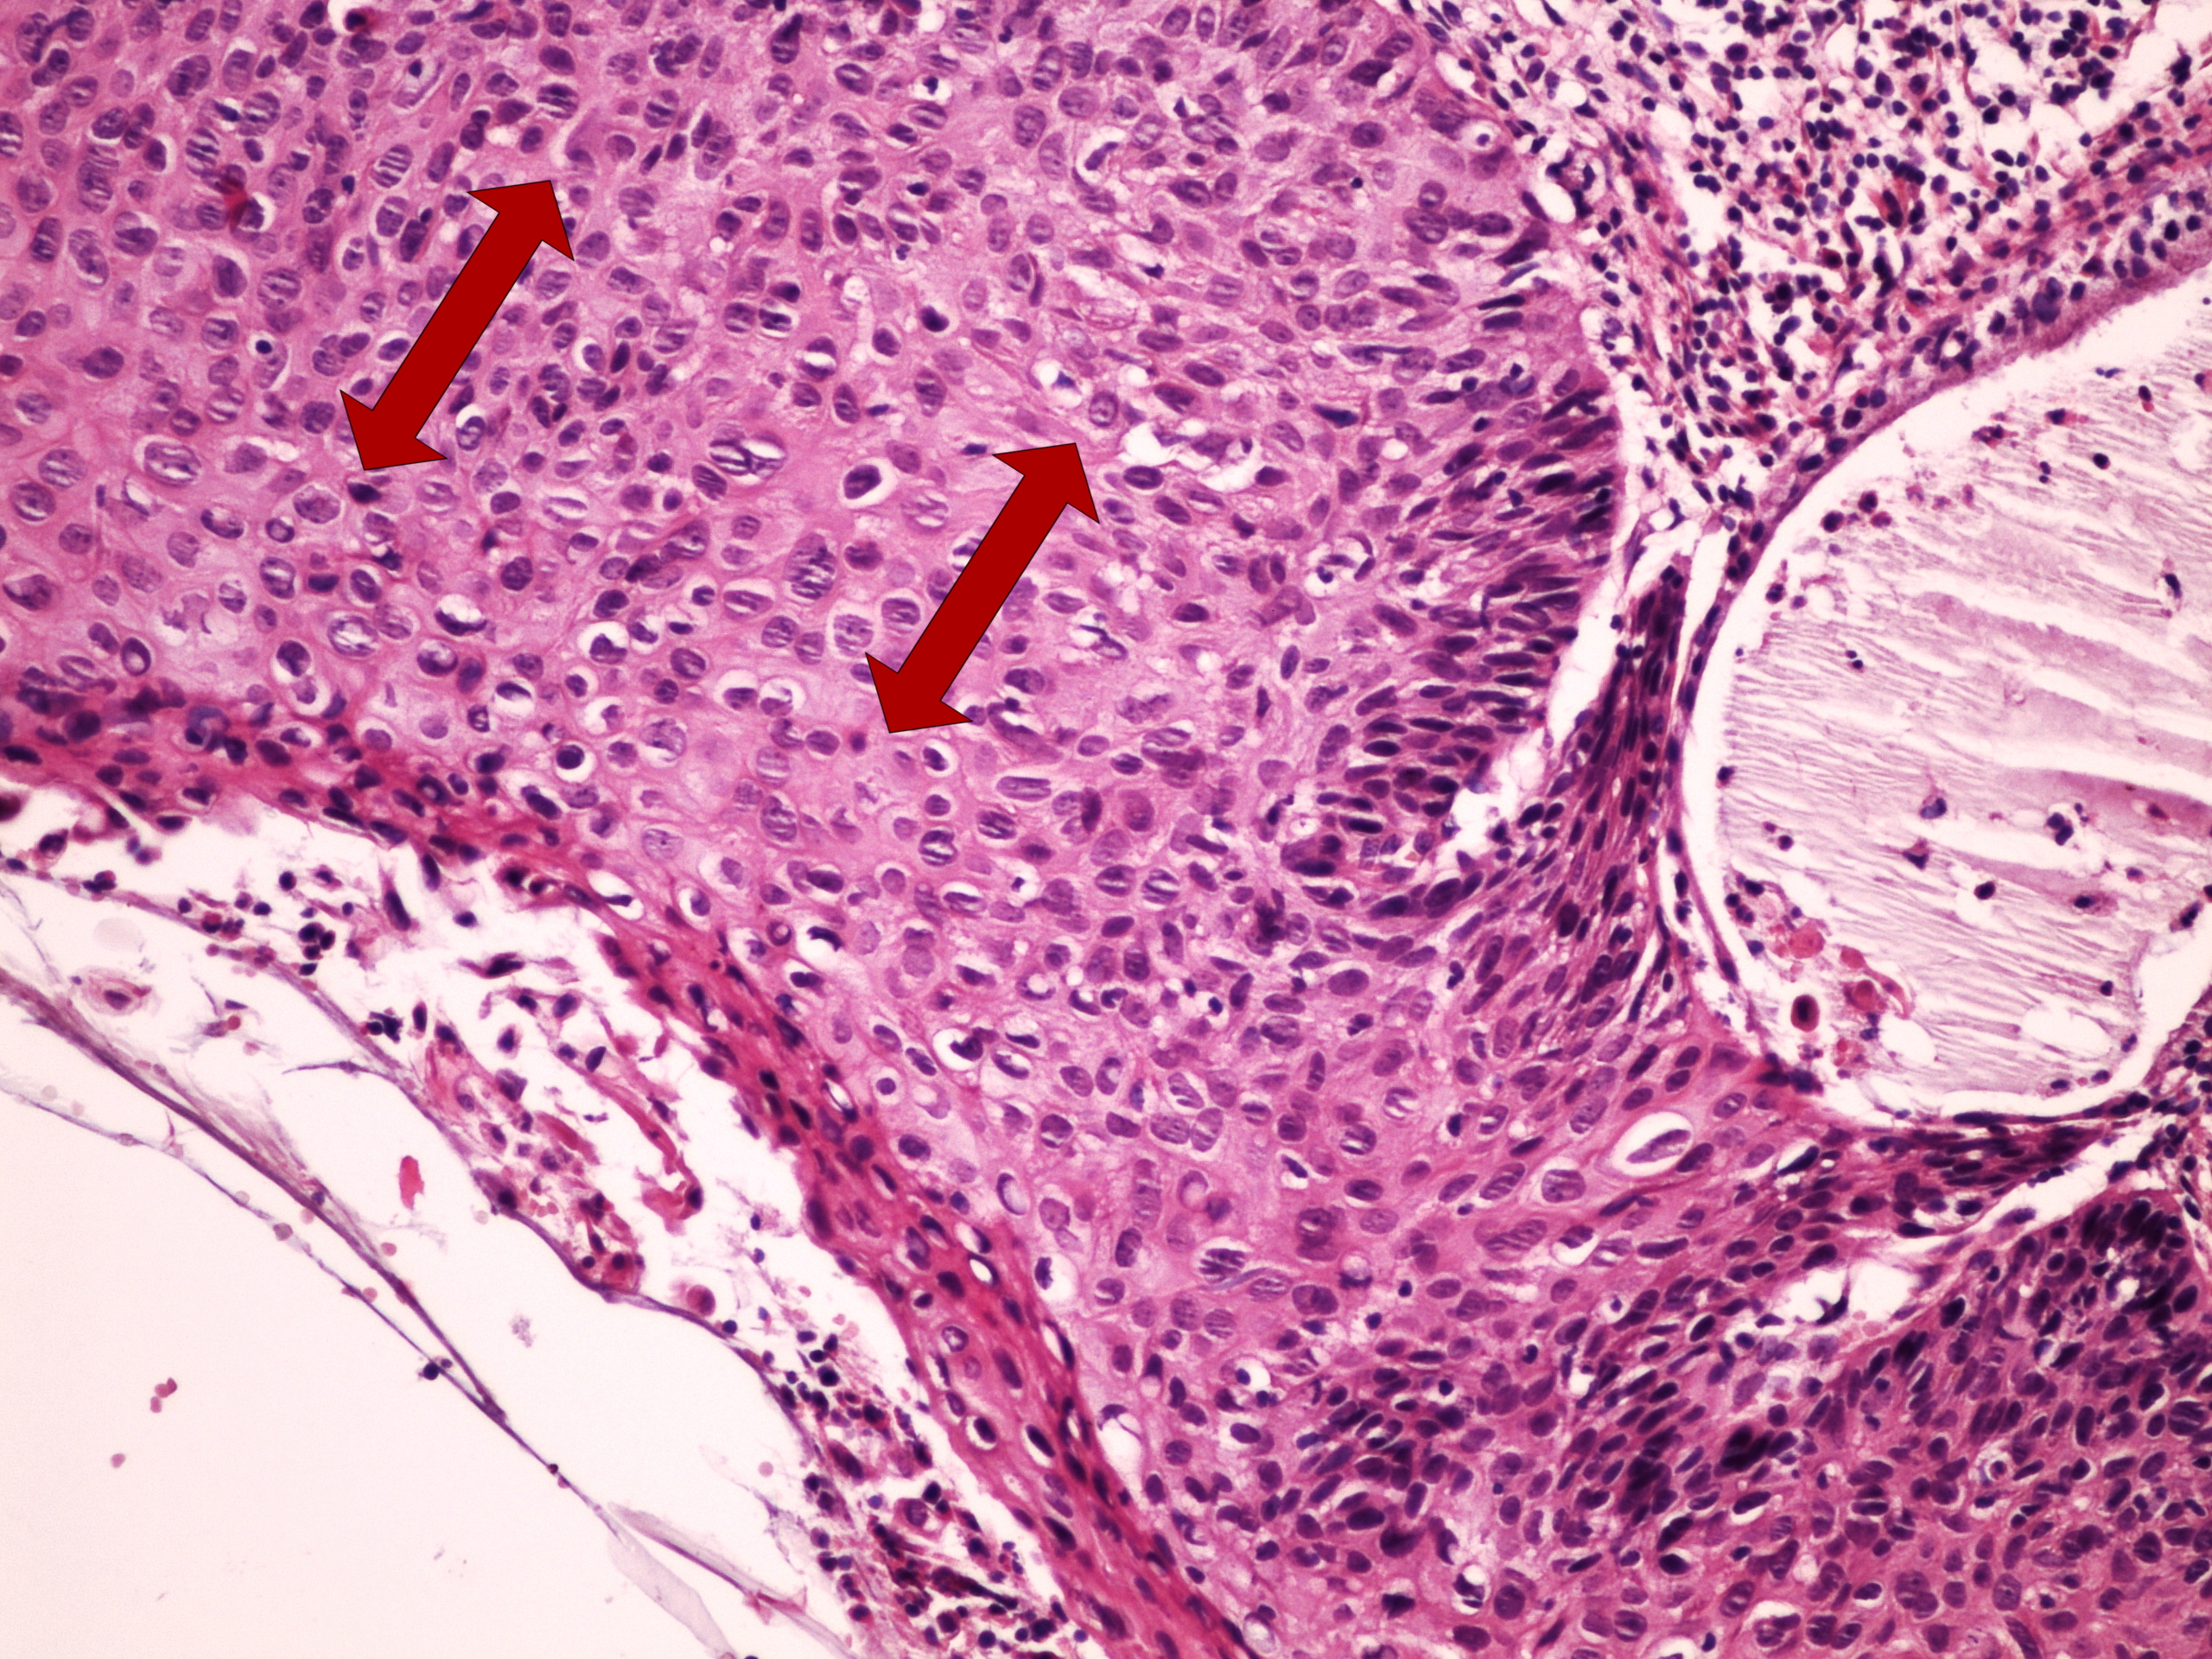

Preparát č.11 a č.12 - Bowenova dermatosa

Struktury

- zánětlivý infiltrát

- hyperparakeratosa a parakeratosa

- těžká dysplazie - ca in situ